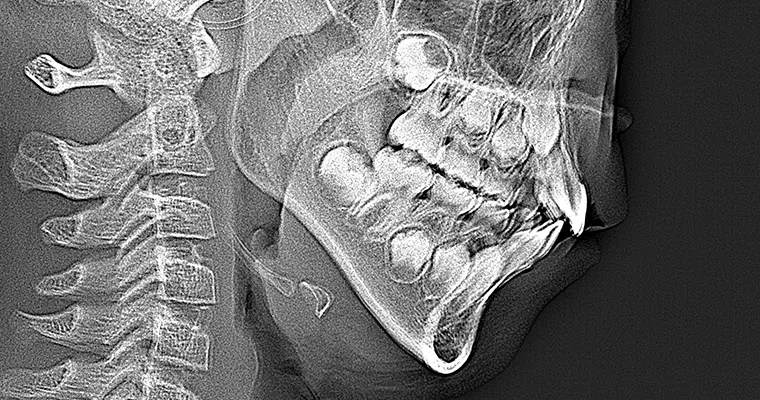

治療前 パノラマレントゲン

治療前 セファロレントゲン